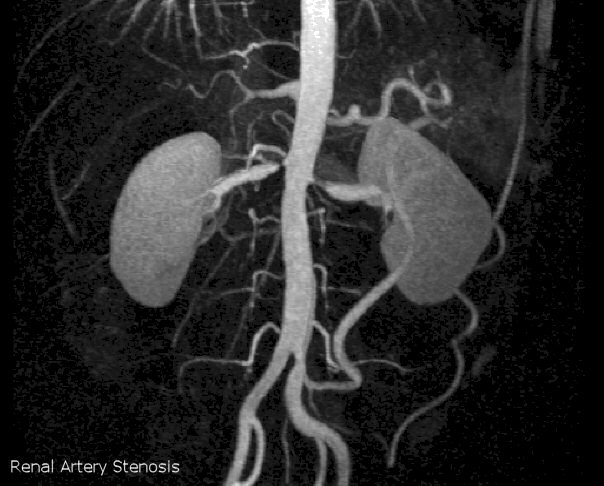

These conditions can usually be excluded by a series of blood tests, 24 hour urine collections, and scans. Before any consideration of fancy tests, the basic investigations include a full blood count to check for anaemia, blood salts (electrolytes), a chest X -ray and an ECG. More recently, cardiac magnetic resonance imaging has been used to exclude most causes of secondary hypertension such as coarctation of the aorta, renal artery stenosis and adrenal tumours (see below).